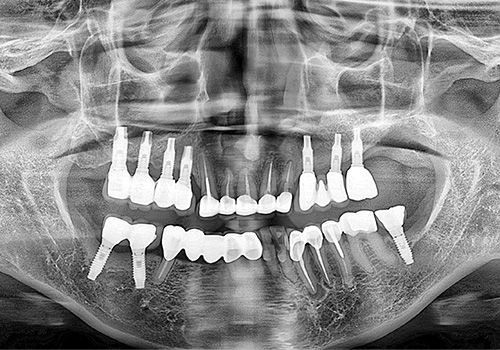

김○영님 임플란트 식립 전

2019년 2월

김○영님 임플란트 식립 후

2019년 11월 -